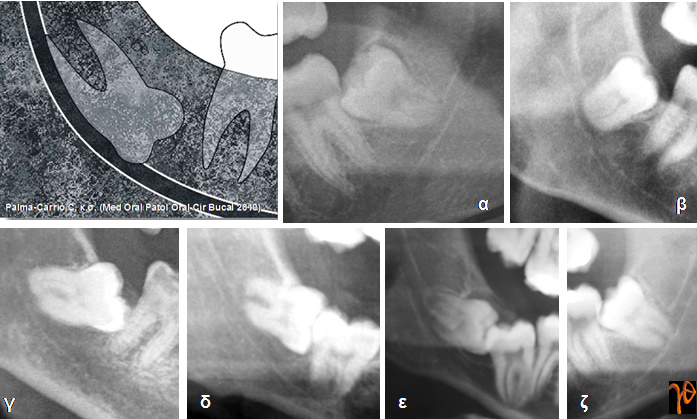

Στις εικόνες που ακολουθούν υπενθυμίζονται κάποιες από αυτές τις περιπτώσεις στις οποίες θα πρέπει να δίνεται ιδιαίτερη προεγχειρητική και χειρουργική προσοχή:

Εικόνα 2. Διακοπή της συνέχειας της λευκής γραμμής του γναθιαίου πόρου [Σχέδιο και Ακτινογραφίες (α-ζ)]